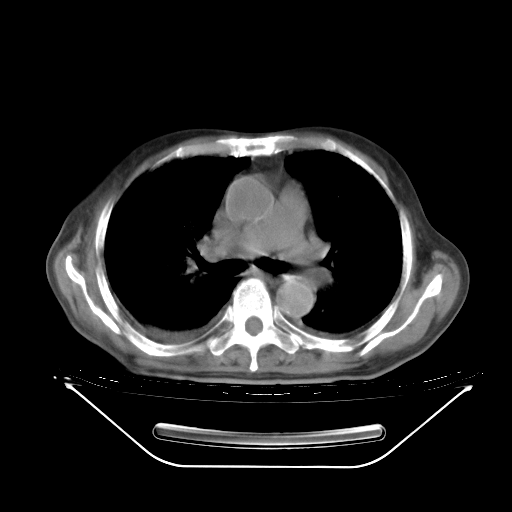

胸腹部CT,诊断意见:左上肺叶钙化灶、左侧胸膜局限性增厚并钙化、胆囊炎。描述部分肺组织呈磨玻璃样改变。